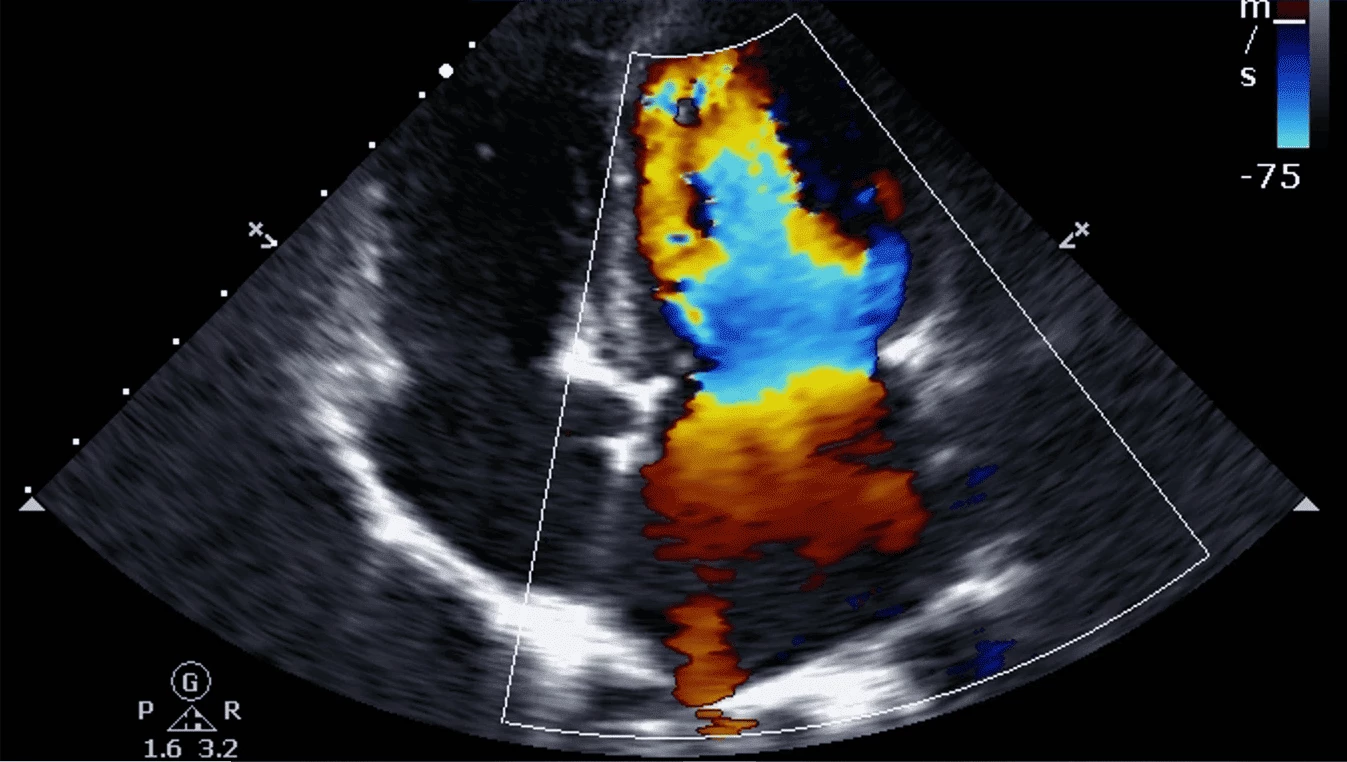

Siêu âm màu tim

Tích hợp các tính năng Doppler tiên tiến, cho phép hiển thị hình ảnh dòng chảy mạch máu chi tiết và rõ ràng.